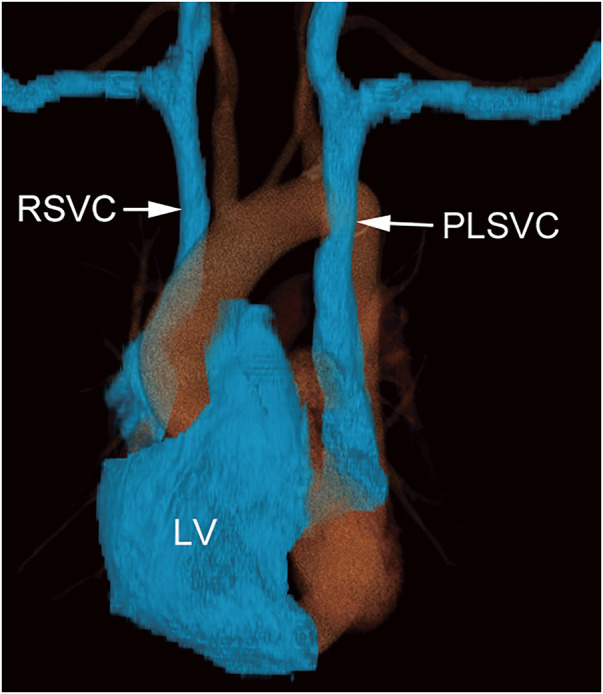

Case presentation: A 75-year-old male patient required a central venous port for chemotherapy and radiation therapy for mid-thoracic esophageal cancer. Preoperative computed tomography images revealed that the PLSVC ran ventrally to the aortic and left pulmonary arteries, directly communicating with the right atrium. A peripherally inserted central catheter (PICC) port was planned. The catheter tip of the PICC port was placed within the left superior vena cava instead of the more common right superior vena cava, because the appropriate vessels could not be identified in the right upper arm. This anomaly necessitated a review of findings on the preoperative imaging and underscored the importance of early detection through echocardiography and radiographic guidance to prevent procedural complications. Reconstructed three-dimensional images and radiography-guided catheterization support the navigation of PICC port insertion.